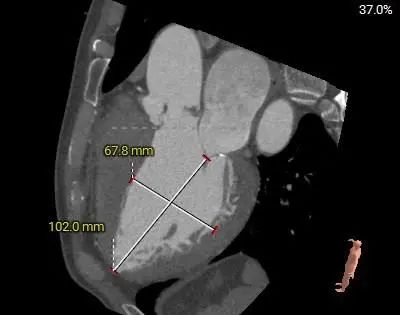

主动脉根部测量

31mm超大瓣环,敞口流出道,瓣膜锚定难度高;结合多平面分析,推荐瓣环上3-4mm开始定位释放。

窦部及STJ内径尚可,升主动脉扩张。

左室内径偏大,EF值36%,心尖部较薄,术中密切关注血流动力学变化,注意加硬导丝位置,避免心室穿孔

左右冠脉高度尚可,冠脉阻挡风险相对较低

轻中度钙化,一定程度上辅助可瓣膜锚定